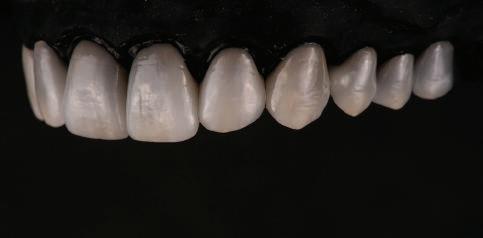

тация на долната челюст. Дъга GUMMETAL с tip-back извивки бе поставена в долната челюст за ниве лиране кривата на Шпее. Случаят бе финализиран с 19x25 SS дъги в горната и долната зъбна дъга за координиране. Преди да се изготви финалният восъ чен моделаж, естетичните и лицеви те характеристики бяха анализирани с помощта на дигитален дизайн на ус мивката, за да се създаде мок-ъп, чии то форма и размери да бъдат одобрени от пациента. Бе оценена фонетиката и бяха заснети лицеви снимки и видеа. Зъ бите бяха изпилени, като препарация та бе изцяло водена от функционалния восъчен моделаж, прехвърлен в устата на пациента. След препарацията восъч ният моделаж бе напаснат и насложен върху препарационния модел и бе фрезо ван от e-max multi bl 1. Циментирането на финалните конструкции бе направе но при изолация с кофердам, следвайки адхезивния протокол. След циментирането бе направено проследяване на оклузията чрез снема не на отпечатъци, монтиране на моде лите в артикулатор в окончателната интеркуспидация и внимателно прове ряване за наличие на блокажи при воде ни движения.

След стабилизира не на ставите и долната челюст в те рапевтична позиция постигнах орто донтски премествания и скелетни ко рекции, които обикновено са възмож ни единствено посредством ортогнат на хирургия. Преминах от аналогов мо дел на работа към изцяло дигитален, за да се хармонизира лицевата естетика чрез Digital Smile Design, като същевре менно обаче изработих функционален аналогов восъчен моделаж и на двете че люсти, за да мога да приложа оклузална та концепция на Славичек. След което напаснах препарациите с аналоговия во съчен моделаж при изцяло дигитални ус ловия с цел фрезоване на короните. Всич ки тези комбинации правят случая из ключително комплексен. В крайна сметка този сложен случай бе лекуван с най-добрата възможна ком бинация от възможности, които ана логовият и дигиталният свят предла гат, за да се постигне красота, която е следствие от отлична функция. ОКЛУЗАЛЕН „БАЛЕТ“ С РОЗОВАТА ЕСТЕТИКА Клиничен случай, победител в категория „Комплексно естетично възстановяване“ в конкурса „Усмивка на годината 2022“ Преди След

7Dental Tribune Bulgarian Edition / октомври 2022 г. Преди лечението Фиг. 1 Фиг. 4 Фиг. 7 Фиг. 10 Фиг. 13 Фиг. 16 Фиг. 17 Фиг. 18 Фиг. 19 Фиг. 20 Фиг. 11 Фиг. 14 Фиг. 12 Фиг. 15 Фиг. 8 Фиг. 9 Фиг. 5 Фиг. 6 Фиг. 2 Фиг. 3

8 Dental Tribune Bulgarian Edition / октомври 2022 г. По време на лечението Фиг. 21 Фиг. 25 Фиг. 30 Фиг. 31 Фиг. 34 Фиг. 38 Фиг. 40 Фиг. 44 Фиг. 48 Фиг. 50 Фиг. 49 Фиг. 46 Фиг. 39 Фиг. 41 Фиг. 45 Фиг. 47 Фиг. 42 Фиг. 43 Фиг. 35 Фиг. 36 Фиг. 37 Фиг. 32 Фиг. 33 Фиг. 26 Фиг. 28 Фиг. 29 Фиг. 27 Фиг. 22 Фиг. 23 Фиг. 24

9Dental Tribune Bulgarian Edition / октомври 2022 г. След лечението За авторите: Д-р Манол Ивчев е създател на COLDY DENT Functional Atelier, завършва дентална медицина във ФДМ, София. Шест години е стажант в ортодонтска практика. Интересите му са изцяло насочени към функционалната дентална медицина. Посещава курсовете на Доусън и Льо Гал. Преминава редица обучения, акредитирани от Института на Славичек във Виена – VieSID. Впоследствие става най-младият инструктор във VieSID. Придобива права да преподава философията на проф. Рудолф Славичек в България. В практиката си се придържа към протоколите на Славичек за функционално лече ние и диагностика, тъй като те са насочени към комплексно лечение. Завършва всички нива за морфология на зъбите и моделаж при Janos Mako. Повишава знанията си по функционална ортодонтия чрез индивидуален курс в Румъния. Д-р Ивчев е и сертифициран зъболекар по лингвална ортодонтия от Катедрата по ортодонтия от Университета по стоматология в Тегу, Южна Корея. Сертифициран е и за лечение на ортодонтски аномалии чрез миофункционални апарати, а също и за ортодонтия, подпомагана от миниимпланти, отново от Университета по стоматология в Южна Корея. Завършва индивидуално обучение по функционална ортодонтия в Университета по дентална медицина в Богота, Колумбия, както и индивидуално обучение по функционална ортодонтия и физиотерапия по про токола на Mariano Rocabado. Има завършено индивидуално обучение по функционална зъботехника и функционален Wax-Up клас I,II и III. Завършва курс за Digital Smile Design и Skin Concept в Люксембург при Christian Coachman, Florin Cofar, Paulo Kano, Josef Kunkela, Livio Yoshinagа. Зт. Leandro Gambogi, Бразилия, завършва зъботехника през 1999 г. Експерт и пионер в дигиталната диагностика. Лектор и инструктор на курсове в областта на дигиталното протезиране. Понастоящем е главен изпълнителен директор и зъботехник в DENTALE DIGITAL LAB. В периода януари 2005 г. – декември 2006 г. завършва бизнес управление и администрация в Methodist University Center Izabela Hendrix. Съавтор на книгата Odontologia Digital: Desafiando os Limites, глава 5: „Дигитално включване във времето. Технология CAD/CAM“. Преминал множество обучения при световноизвестни кли ницисти. Фиг. 51 Фиг. 54 Фиг. 57 Фиг. 58 Фиг. 63 Фиг. 64 Фиг. 65 Фиг. 59 Фиг. 61 Фиг. 62 Фиг. 60 Фиг. 55 Фиг. 56 Фиг. 52 Фиг. 53 Фиг. 66